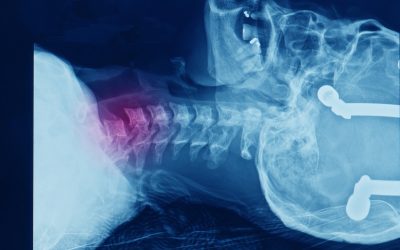

Rtg vratne kralježnice je radiološka dijagnostika kod koje se rendgenskim zračenjem snima vratna kralježnica kako bi se ustanovilo stanje vratne kralježnice. Kod osoba koje rade sjedalački posao za ur